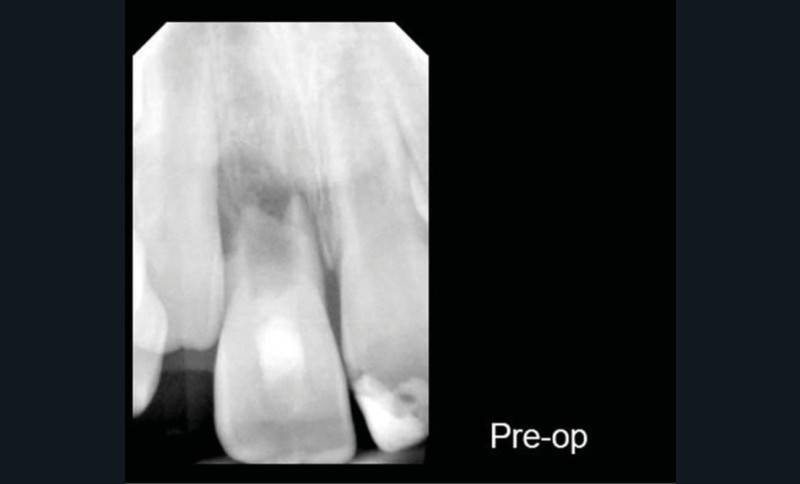

Ce cas clinique est particulier et illustre parfaitement l’évolution que suit l’endodontie depuis une dizaine d’années. Sans entrer dans le détail technique, cette dent expulsée avait été repositionnée dans son alvéole et un premier traitement de régénération intracanalaire tenté. Malheureusement suivi d’un échec. Le jeune âge de la patiente a été une motivation particulière pour tout tenter dans le but, au moins, de gagner du temps. Après plusieurs séances d’hydroxyde de calcium, l’apexification a été réalisée comme cela était possible. Le contrôle à 18 mois confirme que l’acharnement a payé.

Plus que sur l’éventuelle « prouesse technique » – qu’en tant que praticien nous pouvons être tentés de saluer –, il faut s’arrêter sur la facilité qu’a la biologie de stabiliser une situation pourtant désespérée, lorsque les conditions de remise en conditions saines sont mises en place.